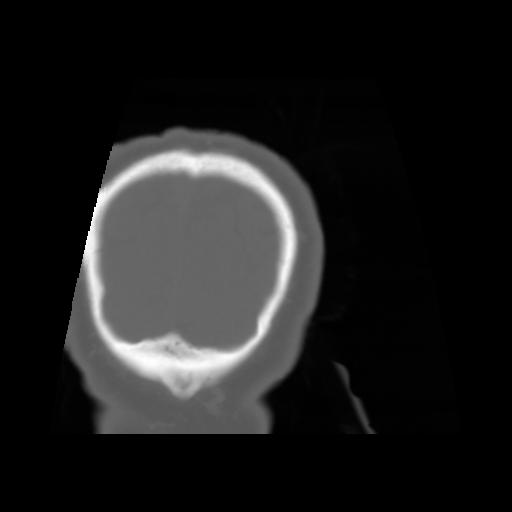

5 CEREBRO,,Coronal,3.000,CEREBRO,Coronal,